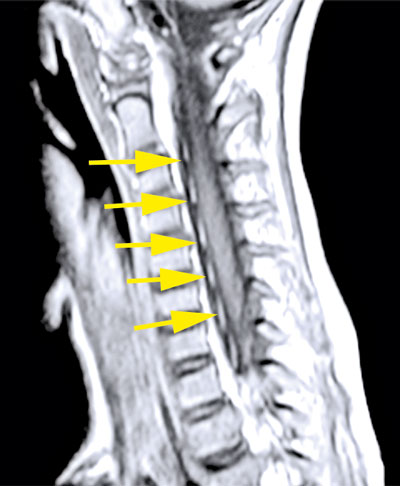

Fall 1. En 9 år gammal flicka sökte på barnakuten efter att ha haft feber i några dagar och vaknat med uttalad svaghet i höger arm. Akut DT-undersökning av hjärna visade normala fynd. Kompletterande MR-undersökning visade signalförändringar i bakre delen av pons och långsträckta signalförändringar i ryggmärgens gråa substans (mer expansiva i halsryggmärgen än i övriga ryggmärgen). Inget patologiskt kontrastmedels­upptag påvisades (Figur 1). MR ingav först misstanke om spinal tumör, men eftergranskning visade en mer tydlig inflammatorisk bild och tumörmisstanken kunde avskrivas. Lumbalpunktion visade lätt pleocytos. Mikrobiologisk utredning i blod och likvor utföll negativ. Prov från feces och nasofarynx togs inte.

Figur 1 (fall 1). Vid initial MR-undersökning visade T2-viktad sekvens expansiva signalförändringar över hela cervikala ryggmärgen (första bilden) jämfört med mer kaudala delar; axialt T2-viktad sekvens i höjd med C4 visade mer expansiv grå substans (andra bilden). T2-viktad FLAIR (fluid attenuated inversion recovery) visade förhöjd signal i bakre delen av pons (tredje bilden). Vid MR-undersökning 10 dagar senare kunde T2-viktad sekvens inte påvisa signalförändringarna i ryggmärgen (fjärde och femte bilden). På T2-viktad FLAIR har signalförändringarna i pons gått i regress (sista bilden).